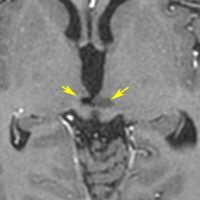

血清HCGが2.1mIU/ml,尿崩症で発症した思春期男児です。石灰化はありませんし,脂肪組織なども混在しません。生検術をしなくてもgerminomaと診断できます。でも簡単なので,経鼻的な生検術を行った方がいいです。